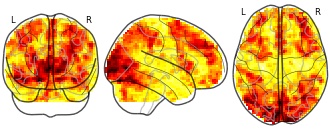

BrainPedia: HCP_task007_sub061

EmailClick to copy linkLink copied Cite(2018). BrainPedia: HCP_task007_sub061 [Dataset]. http://identifiers.org/neurovault.image:32273niftiAvailable download formatsUnique identifierhttps://identifiers.org/neurovault.image:32273Dataset updatedApr 26, 2018License

Cite(2018). BrainPedia: HCP_task007_sub061 [Dataset]. http://identifiers.org/neurovault.image:32273niftiAvailable download formatsUnique identifierhttps://identifiers.org/neurovault.image:32273Dataset updatedApr 26, 2018LicenseCC0 1.0 Universal Public Domain Dedicationhttps://creativecommons.org/publicdomain/zero/1.0/

License information was derived automaticallyDescriptionCollection description

BrainPedia is a collection of SPMs obtained from about 30 protocoles from OpenfMRI, the Human Connectome Project and Neurospin research center that map a wide set of cognitive functions.

Subject species

homo sapiens

Modality

fMRI-BOLD

Analysis level

single-subject

Cognitive paradigm (task)

working memory fMRI task paradigm

Map type

Z